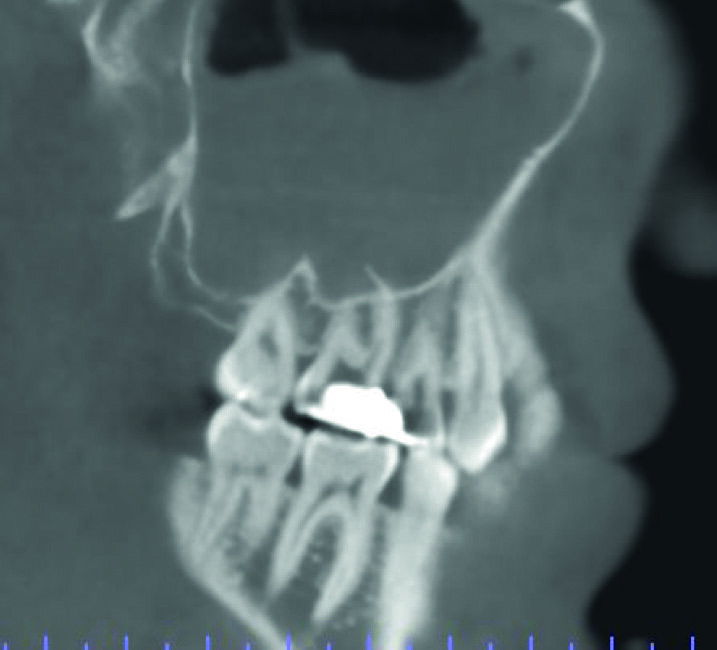

Un patient avait été adressé au cabinet en raison de problèmes associés à la fracture d’une lime. Il était pilote de ligne et se plaignait d’écoulements nasaux purulents lorsqu’il était en vol. La radiographie pré-opératoire (Fig. 1) a distinctement montré la présence de deux fragments d’une lime fracturée dans les canaux mésiaux et d’un cône traversant l’apex de la racine palatine. Après l’imagerie CBCT avec iCAT, il est apparu clairement que le sinus gauche était presque totalement rempli de liquide inflammatoire (Fig. 2) et que le cône présent dans le canal palatin pénétrait dans le sinus. Sur l’image de reconstruction multi planaire (MPR), nous pouvions également distinguer les deux fragments de lime fracturée dans les deux canaux mésiaux (Figs. 3 et 4) et aussi un autre fragment dans le sinus sans aucun contact avec le canal (Fig. 5). L’utilisation de différents filtres nous a permis de visualiser les fragments de lime (Figs. 6–9), ainsi que l’inflammation et le fragment de lime fracturée à l’intérieur du sinus. Nous avons également mieux perçu la position du cône qui émergeait du canal palatin et pénétrait dans le sinus.